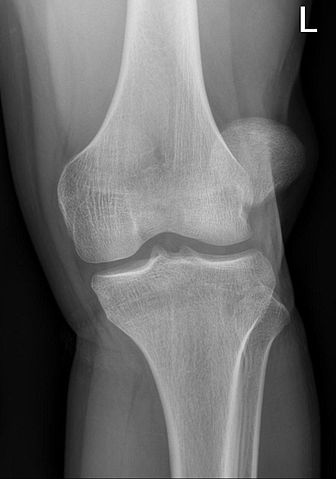

- Αρχικώς ο ασθενής θα πρέπει να κάνει πάντα ακτινογραφίες προ και μετά ανατάξεως του εξαρθρήματος για τον έλεγχο της θέσης ανάταξης και τυχόν συνοδών βλαβών. Η ακτινογραφία πριν την ανάταξη δεν είναι πάντοτε εφικτή λόγω συνθηκών παρόλα αυτά ο ασθενής πάντα θα πρέπει να υποβάλλεται σε έλεγχο τουλάχιστον μετά την ανάταξη.

- Αξονική και μαγνητική τομογραφία χρειάζονται για τον έλεγχο ανατομικών ανωμαλιών του γόνατος που οδηγούν σε εξάρθρημα (π.χ αβαθής τροχιλία) και άλλων βλαβών που τυχόν προέκυψαν (π.χ οστεοχόνδρινα ελεύθερα τεμάχια, κακώσεις καθεκτικών και πλαγίων συνδέσμων).